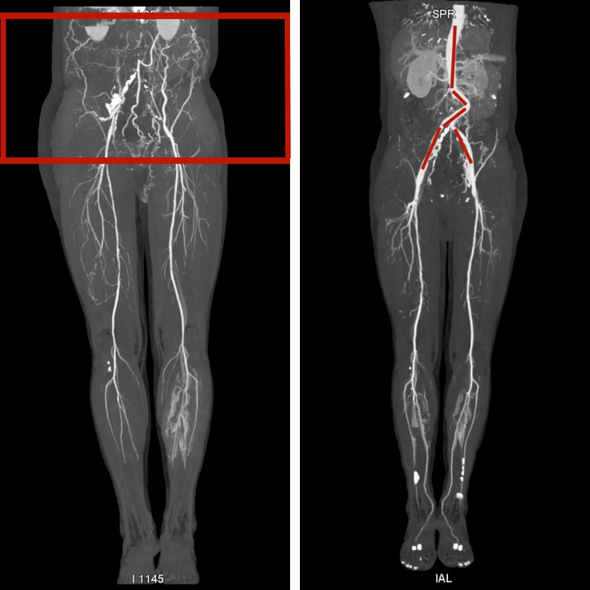

术前(腹主动脉闭塞)、术后(人工血管搭桥)影像对比

近日,患者赵先生因为双下肢麻木发凉间歇性跛行3年,近一年加重,来到我院血管外科就诊。经相关检查发现,赵先生下肢超声考虑近心端狭窄或闭塞,右下肢股总动脉及股浅动脉多发狭窄。随之以“下肢动脉硬化闭塞症”收入院。入院后完善相关检查,腹部及下肢CTA提示:腹主动脉远端、左侧髂总动脉、右侧髂总动脉近段闭塞并周围多发侧支形成。综合评估病程病情,采取人工血管搭桥手术最为适宜。